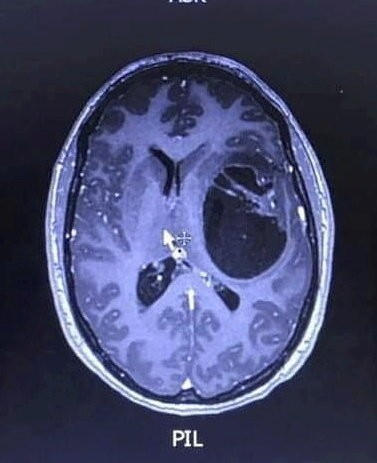

Bývalá farmaceutická pracovníčka opísala, že bola spočiatku úplne zmätená a vystrašená. Do nemocnice ju priviezli v pyžame bez osobných vecí, obklopenú lekármi, ktorí sa jej pýtali otázky, na ktoré sotva dokázala reagovať. Keď jej ukázali snímku mozgu s nádorom, bola zdrvená. Lekári jej povedali, že bez liečby by mohla žiť len niekoľko mesiacov, s liečbou možno 12 až 18.